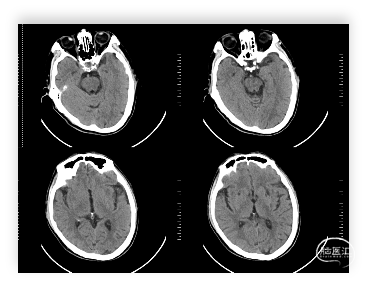

头颅CT:双侧基底节及双侧额叶多发腔隙性脑梗塞;左侧上颌窦炎。

头颅MRI:左侧额顶叶急性脑梗塞;桥脑左份、双侧基底节、右侧脑室旁及双侧额叶多发腔隙性脑梗塞;双侧脑室旁及额顶叶轻度白质脱髓鞘;双侧上颌窦、筛窦、蝶窦炎;脑MRA示①右侧椎动脉纤细(变异)②左侧大脑后动脉P2段局部狭窄③左侧颈内动脉眼段局部严重狭窄④脑动脉轻度硬化改变,请结合临床及其他检查协诊。

入院时头颅CT